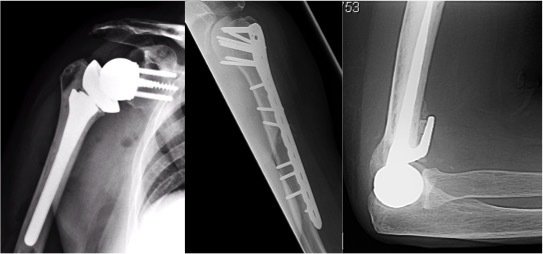

Fellowship Montage

The Fellow will be exposed to all aspects of shoulder and elbow surgery including arthroscopic procedures, arthroplasty, trauma and revision surgery. There are regular weekly elective and upper limb trauma lists with both of the supervising consultants. There is the opportunity for parallel and independent operating as experience allows.